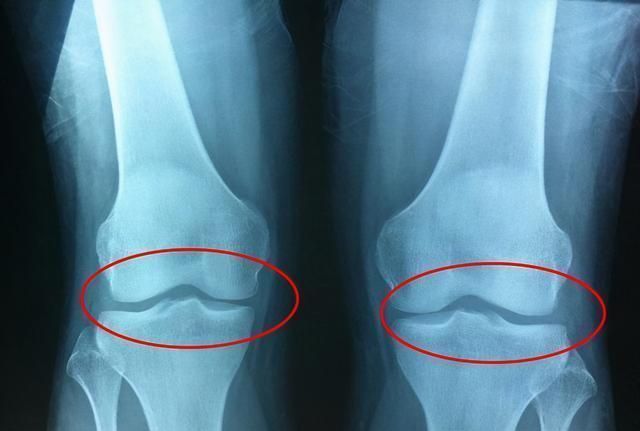

发育过早这里说的发育过早,可不是指女生相对于男生,而是同龄同性之间的比较。如果孩子远超于发育水平,那么家长就要担心他将来的身高了。因为发育过早会导致骨骼线提前闭合,骨骼线一旦闭合,孩子就再也不会长高了。导致发育过早的因素有很多,有两种比较常见,也就是营养过剩和激素的原因。当家长发现自家孩子的发育速度太过迅猛的时候,应该检查一下他的日常饮食,看看是否存在这些问题,及时调整回来,不要等到骨骼线闭合之后再来后悔。